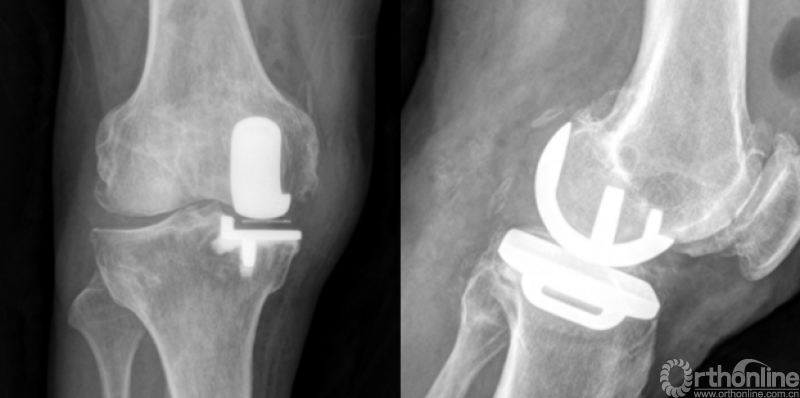

结果表明FAMA线与Akagi线基本平行,其夹角为4.272±0.552°。胫骨截骨块和胫骨假体的AP、ML长度无显著差异(AP差值0.007±0.154cm,p=0.674,ML差值0.020±0.195cm,p=0.155)。两组间的AP、ML长度无显著差异(AP:p=0.281,0.741,0.672,0.849,0.287;ML:p=0.3,0.866,0.085,0.255,0.09;假体型号由AA至D)。两组间的ML/AP比值无显著差异(p=0.141,0.646,0.255,0.607,0.384;假体型号由AA至D)。两组胫骨假体的内外侧位置(组1:0.87±0.03,组2:0.86±0.03,p=0.156)和外旋角度(组1:6.88±2.08°,组2:6.68±2.22°,p=0.746)无显著差异。

4、术后影像学检查示,假体覆盖良好,假体外侧缘与Akagi线基本平行,未出现过度旋转。